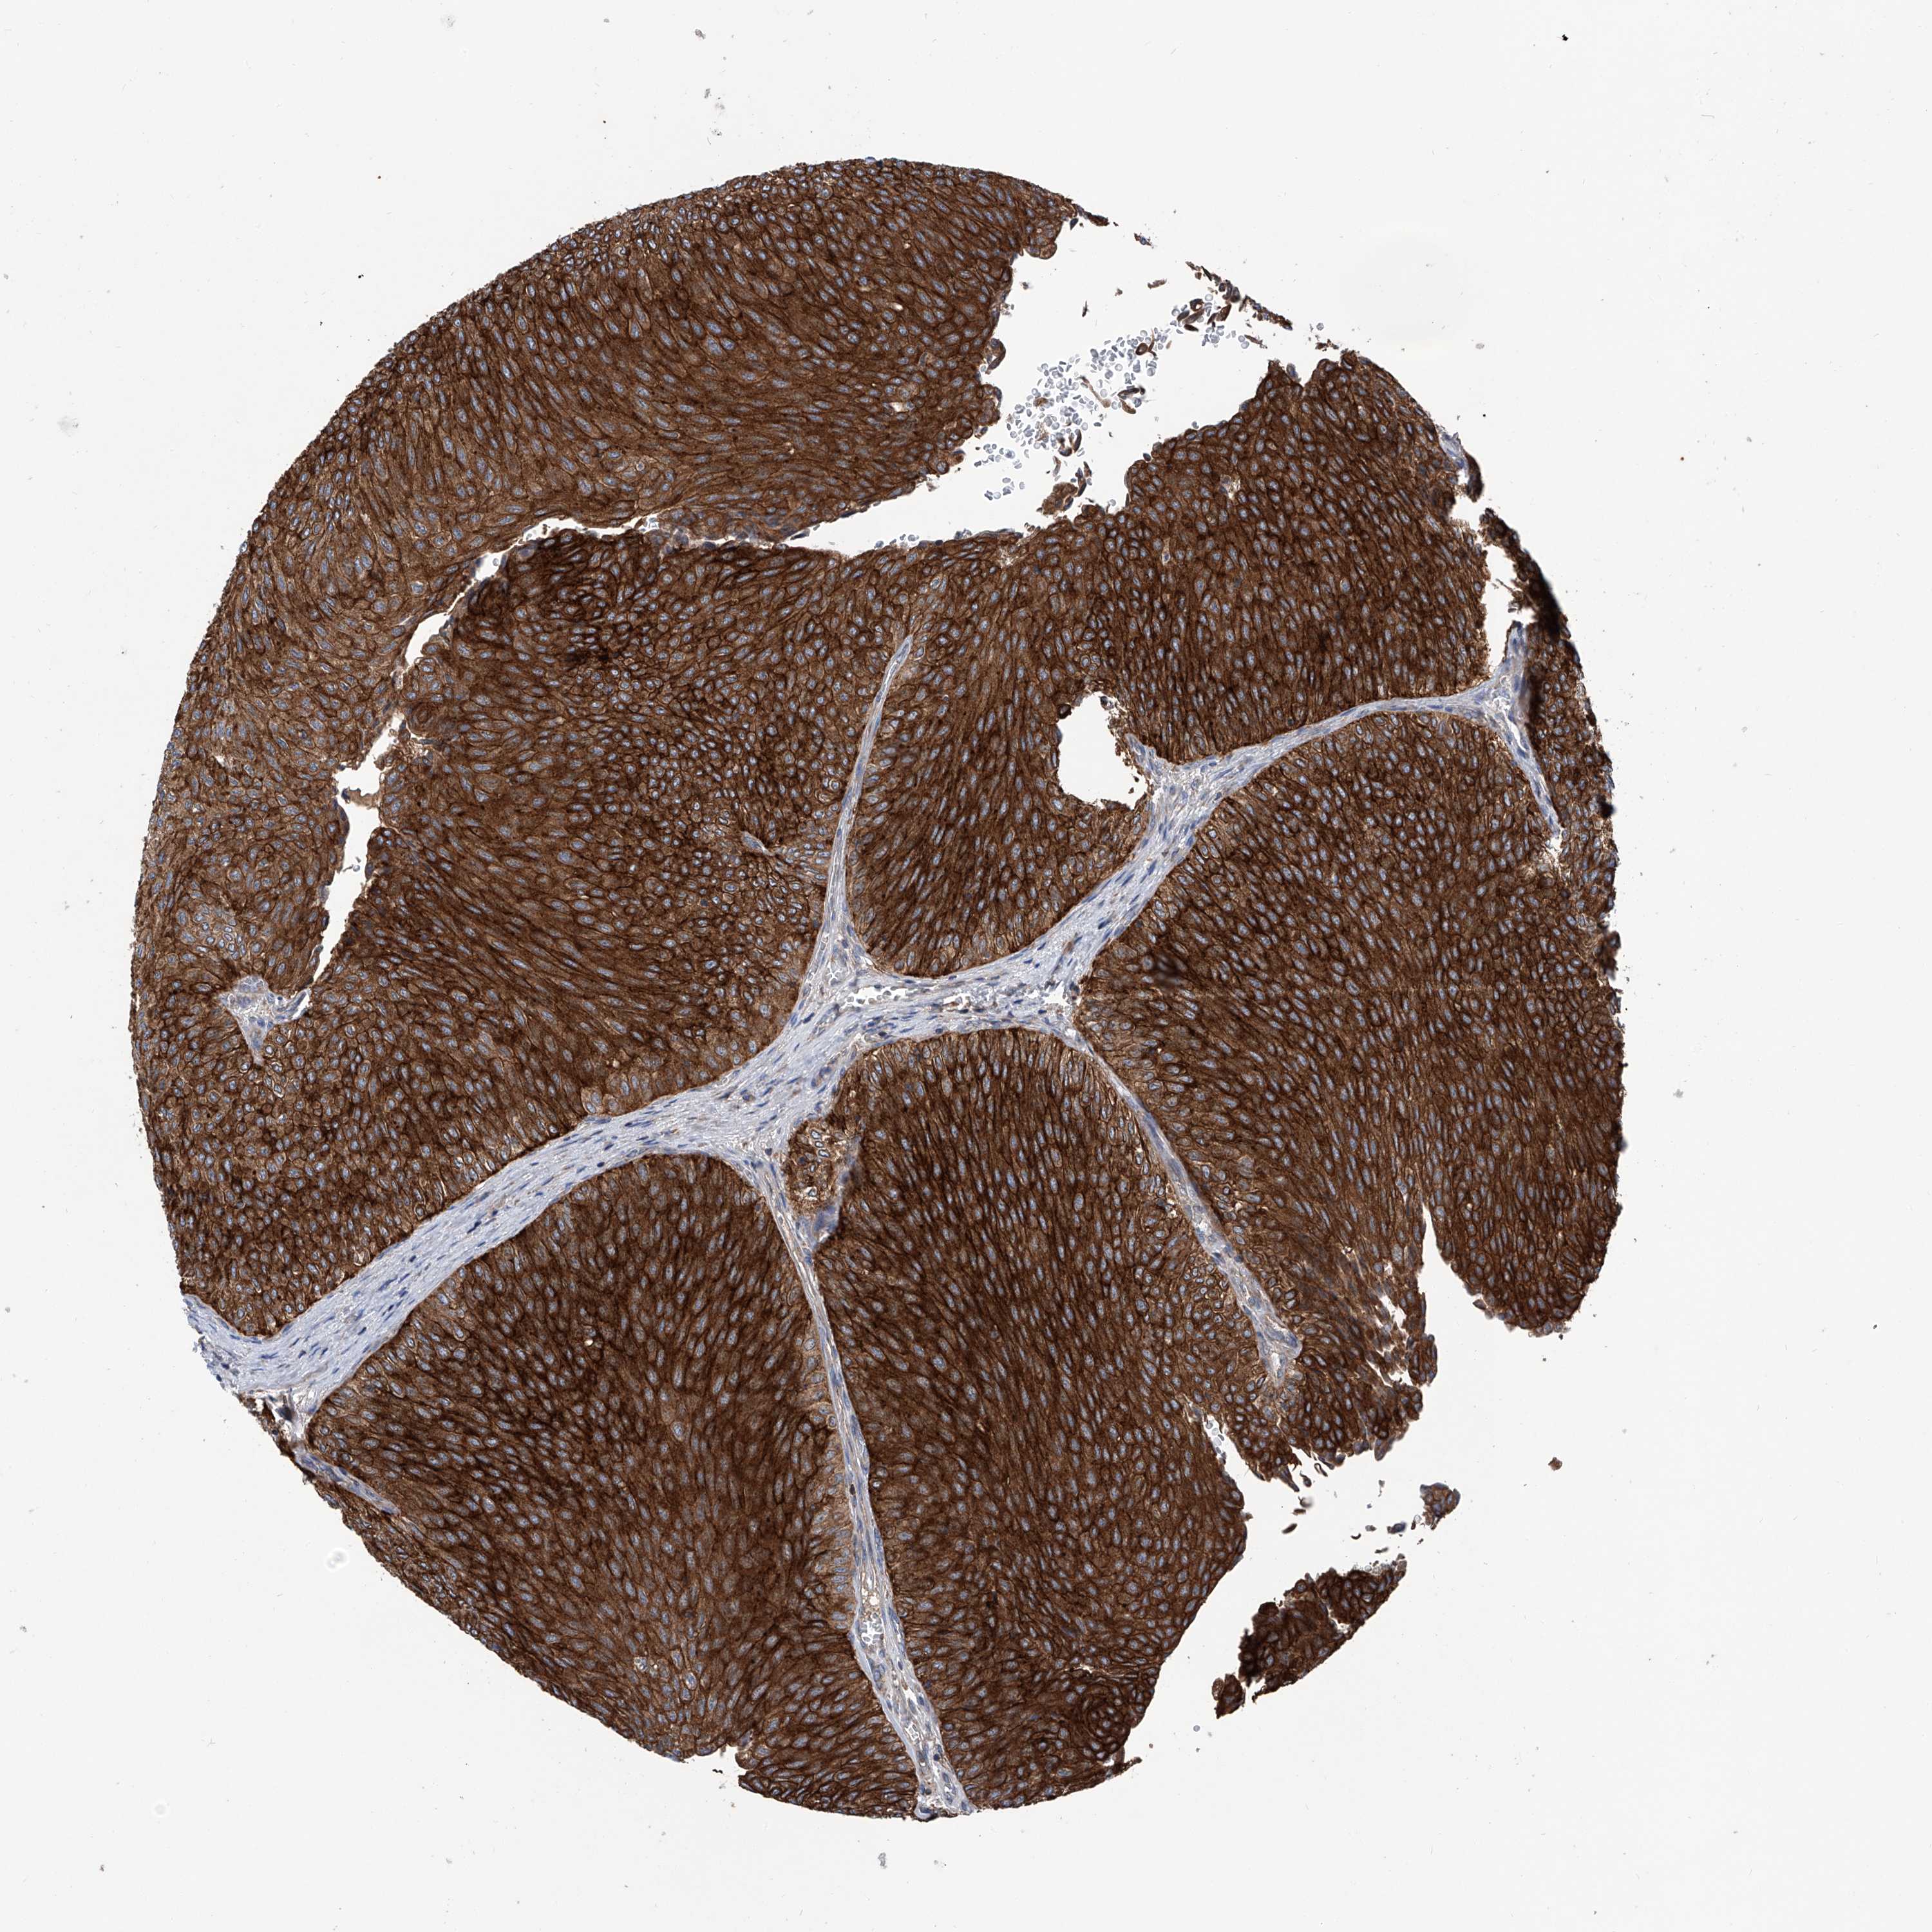

UROTHELIAL CANCER - Protein expressioni

A mouse-over function shows sample information and annotation data. Click on an image to view it in a full screen mode. Samples can be filtered based on level of antibody staining by selecting one or several of the following categories: high, medium, low and not detected. The assay and annotation is described here.

Note that samples used for immunohistochemistry by the Human Protein Atlas do not correspond to samples in the TCGA dataset.

Antibody stainingi

Antibody staining in the annotated cell types in the current human tissue is reported as not detected, low, medium, or high, based on conventional immunohistochemistry profiling in selected tissues. This score is based on the combination of the staining intensity and fraction of stained cells.

Each image is clickable and will lead to virtual microscopy that enables deeper exploration of all samples and also displays staining intensity scores, fraction scores and subcellular localization as well as patient and tissue information for each sample.

Antibody HPA031608

Antibody HPA031609

Antibody HPA031610

Urothelial carcinoma, Low grade

Urothelial carcinoma, High grade